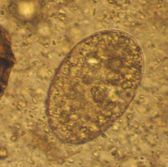

家畜に寄生する主要原虫一覧

鶏●盲腸コクシジウム(Eimeria tenella)汚染常在、孵化後数日で発症、高致死率、要予防●小腸コクシジウム(Eimeria sp)汚染常在、高発症率、要常時予防●ロイコチドゾーン(Leucocytozoon caulleryi)ヌ...